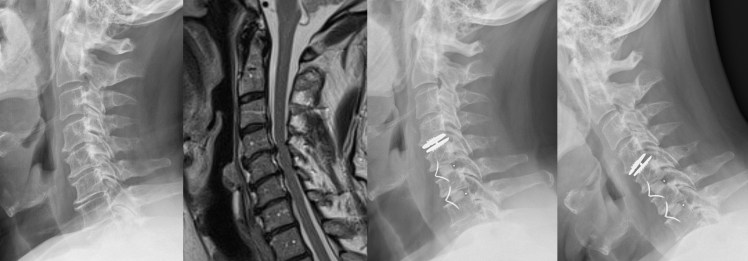

The discectomy goes along with a cervical arthrodesis with anterior approach, has proven its profit. The arthodesis of a defined cervical level leads to an overuse of the adjacent levels (intervertebral discs) and a precocious degeneration of those discs.

An arthrodesis of several cervical levels could limit the function of the cervical spine (flexion, extension, lateral flexion and rotations).

The cervical disc prosthesis maintains or restores the mobility of the adjacent cervical levels and therefore limits or avoids these problems.

Hybrid stabilization with fusion and cervical disc replacements